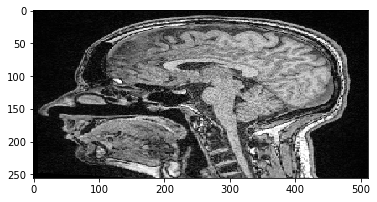

Ahora extraeremos un corte Z del conjunto de datos 3D y lo visualizaremos. En el sistema 012, tomamos un corte de la pila en la primera dimensión (índice 0). Tiene la posición de corte Z=100 (sistema ZYX) o posición 100 a lo largo de la dimensión 0 (sistema 012).

slice = image[100]

cle.imshow(slice)